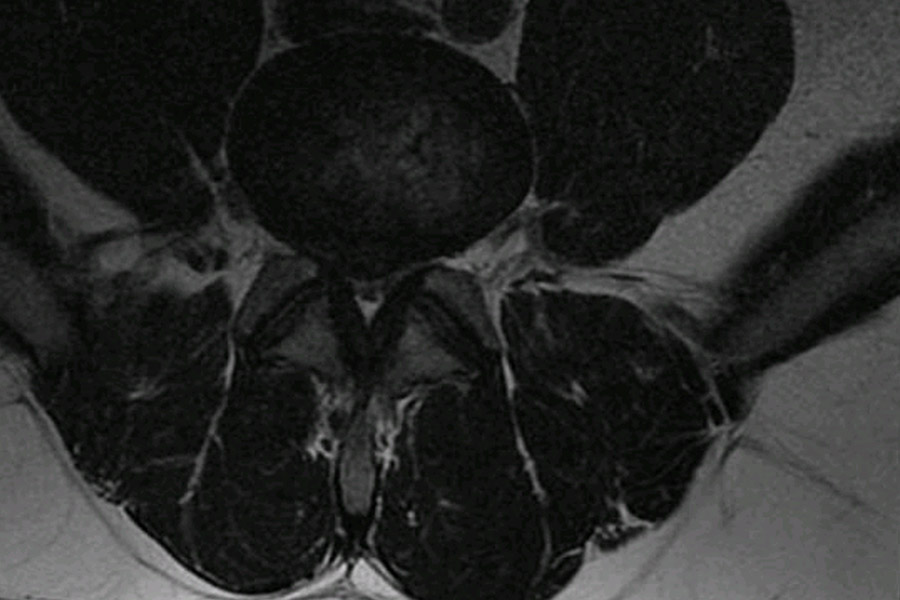

Caso clínico: endoscopia de columna multinivel L4L5 y L5S1

Los síntomas que presentaba el paciente eran dolores acentuados en las piernas, claudicación a la marcha y calambres y hormigueos en las piernas.

Durante la intervención quirúrgica, se abordarán los dos niveles mediante la técnica de endoscopia de columna.